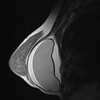

Kết quả phim chụp não của một bệnh nhân ngộ độc rượu Methanol đang điều trị tại Bệnh viện Bạch Mai bị tổn thương nặng nề. (Ảnh: Thùy Giang/Vietnam+)

Kết quả phim chụp não của một bệnh nhân ngộ độc rượu Methanol đang điều trị tại Bệnh viện Bạch Mai bị tổn thương nặng nề. (Ảnh: Thùy Giang/Vietnam+) Thống kê của Cục An toàn Thực phẩm (Bộ Y tế) cho thấy số ca ngộ độc rượu Methanol đang có xu hướng gia tăng nhanh do tình trạng lạm dụng rượu tràn lan. 10 năm qua, toàn quốc có 382 người bị ngộ độc do sử dụng rượu không an toàn, làm 98 người chết (thống kê này không bao gồm ca ngộ độc rượu lẻ tẻ).